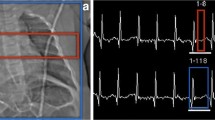

Cardiac MRI is technically challenging in children. Proper acquisition requires the use of ECG gating, which may be technically challenging in infants with rapid heart rate or in patients with pacemakers. Sequences have to be adapted depending on the patient’s ability to breathe hold and their size for proper contrast enhanced MRI angiography [22, 23]. When combined with MRI, respiratory gating of the PET component is possible, but the use of a respiratory belt remains more efficient than gating with MR-based navigators [24, 25].

The Norwood staged palliation for HLHS consists of three interventions. The first stage, performed shortly after birth, reestablishes an unobstructed systemic circulation using the right ventricle. To achieve this, the main pulmonary artery is transected and used to enlarge the hypoplastic aortic arch (the Damus–Kaye–Stansel procedure) (Fig. 21.2). The interatrial septum is excised to allow unobstructed pulmonary venous return to the systemic (right) ventricle. Since the pulmonary arteries are not connected to the right ventricle, an alternative source of pulmonary blood flow must be created, either by a modified BT shunt or a small conduit between the right ventricle and pulmonary arteries (Sano conduit) (Fig. 21.3). The second stage of the Norwood palliation consists of a bidirectional Glenn and is performed typically around 6 months of age, when pulmonary resistances have decreased. The third stage consist of a Fontan procedure, where the inferior vena cava is connected to the pulmonary artery. Following this last stage, all deoxygenated blood from the venous system flows through the lungs. This last step is typically executed around 4 years of age, when the pulmonary arteries are mature enough to accommodate a large conduit [41].

18F-FDG PET/CT of a 1-month-old patient with left ventricle hypoplasia (*). 18F-FDG CTAC images were fused with cardiac CT with contrast (a) and three-dimensional cardiac CT reconstructions (b). Norwood procedure with a Blalock–Taussig (BT) shunt (long thin arrow) between the right subclavian artery and right pulmonary artery (short thin arrow). Damus–Kaye–Stansel (DKS) procedure for creation of the neoaorta, with anastomosis of the main pulmonary artery (open arrow) and hypoplastic native aorta (arrow head)

18F-FDG PET/CT performed in a 2-year-old girl with left ventricular and aortic hypoplasia, status post Norwood–Sano procedure. 18F-FDG CT AC images fused with: cardiac CT with contrast (a), cardiac catheterization image (b) and sagittal FDG CTAC PET/CT (c). Visible reconstructed aortic arch (long thin arrow), Sano shunt (open arrow) and hypoplastic left ventricle (arrowhead). When interpreting 18F-FDG PET/CT, specifically in children with congenital heart disease, correlation with other modalities is paramount